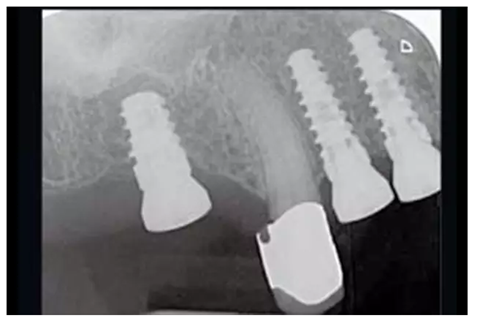

圖16:種植后4個月,放射線檢查RatioPlant種植體的骨結(jié)合情況。

圖17& 18:Katharina Dietz-Epple醫(yī)生(Aalen, Germany)完成的冠修復(fù)(上頜)及可摘局部義齒修復(fù)(下頜)。